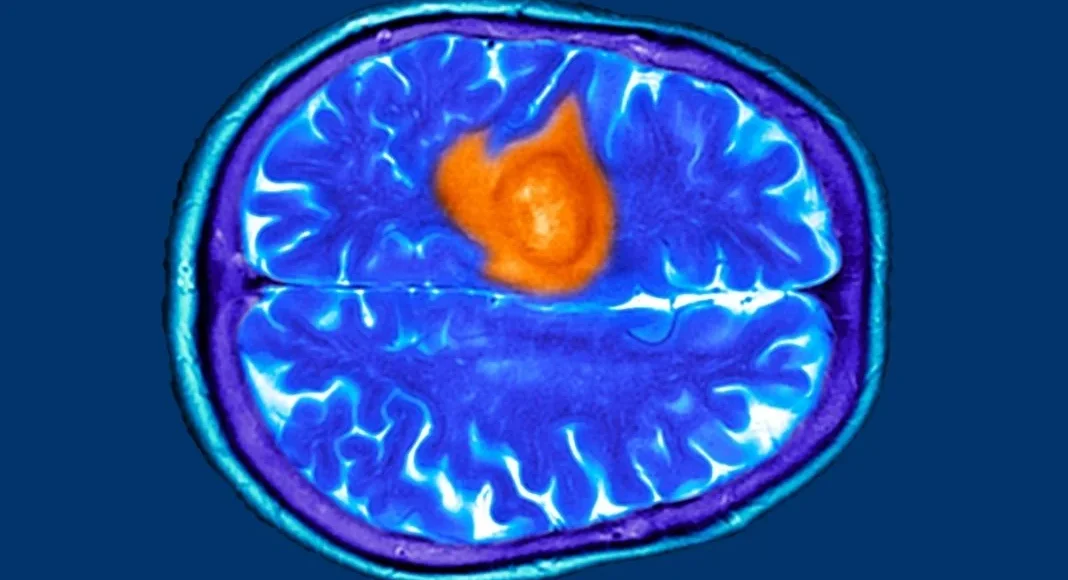

Σύμφωνα με την Laura Standen, διδακτορική ερευνήτρια στο Ινστιτούτο Wolfson σε άρθρο που δημοσιεύει αναφέρεται στα 7 προειδοποιητικά σημάδια του καρκίνου του εγκεφάλου. Όπως σημειώνει η ίδια ως μέρος της έρευνάς της, την οποία μπορείτε να βρείτε εδώ, με όσους ασθενείς έχει μιλήσει κατά τη διάρκεια της ακαδημαϊκής της καριέρας, όλοι της ανέφεραν ένα κοινό στοιχείο.